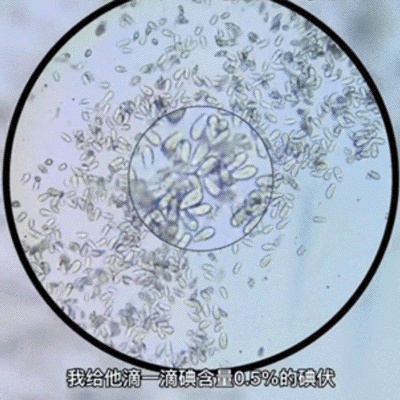

早前有网友在网上分享了碘伏的除菌微观视角,结果发现,原本活跃的微生物在滴入一滴碘伏后,瞬间团灭。

这个速度让评论区沸腾了,网友纷纷称叹碘伏是“强者中的强者”。

图源自@细菌哥陪看显微镜